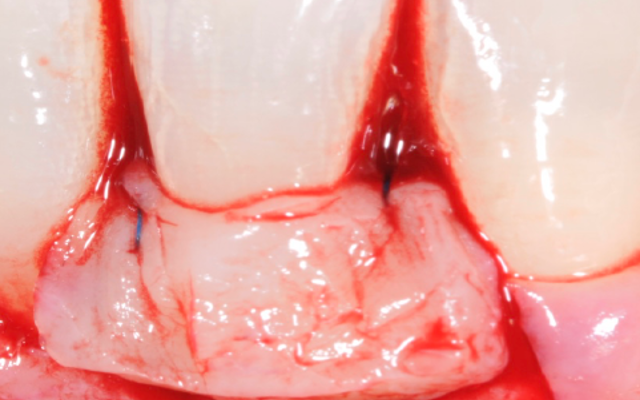

The harvested gum graft is sutured or tied up on the exposed root surfaces to cover the receded or exposed roots of the teeth (Figure 12D). There is also a relatively new technique where a collagen graft, usually derivative from porcine (xenograft), manufactured by a dental company is used to cover the root surface.

This is to avoid the harvesting of gum from the roof of the mouth, producing less surgical pain after the procedure. The predictability of this “out of the packet gum graft” is still being investigated as there is limited research available when compared to the patients’ harvested gum.